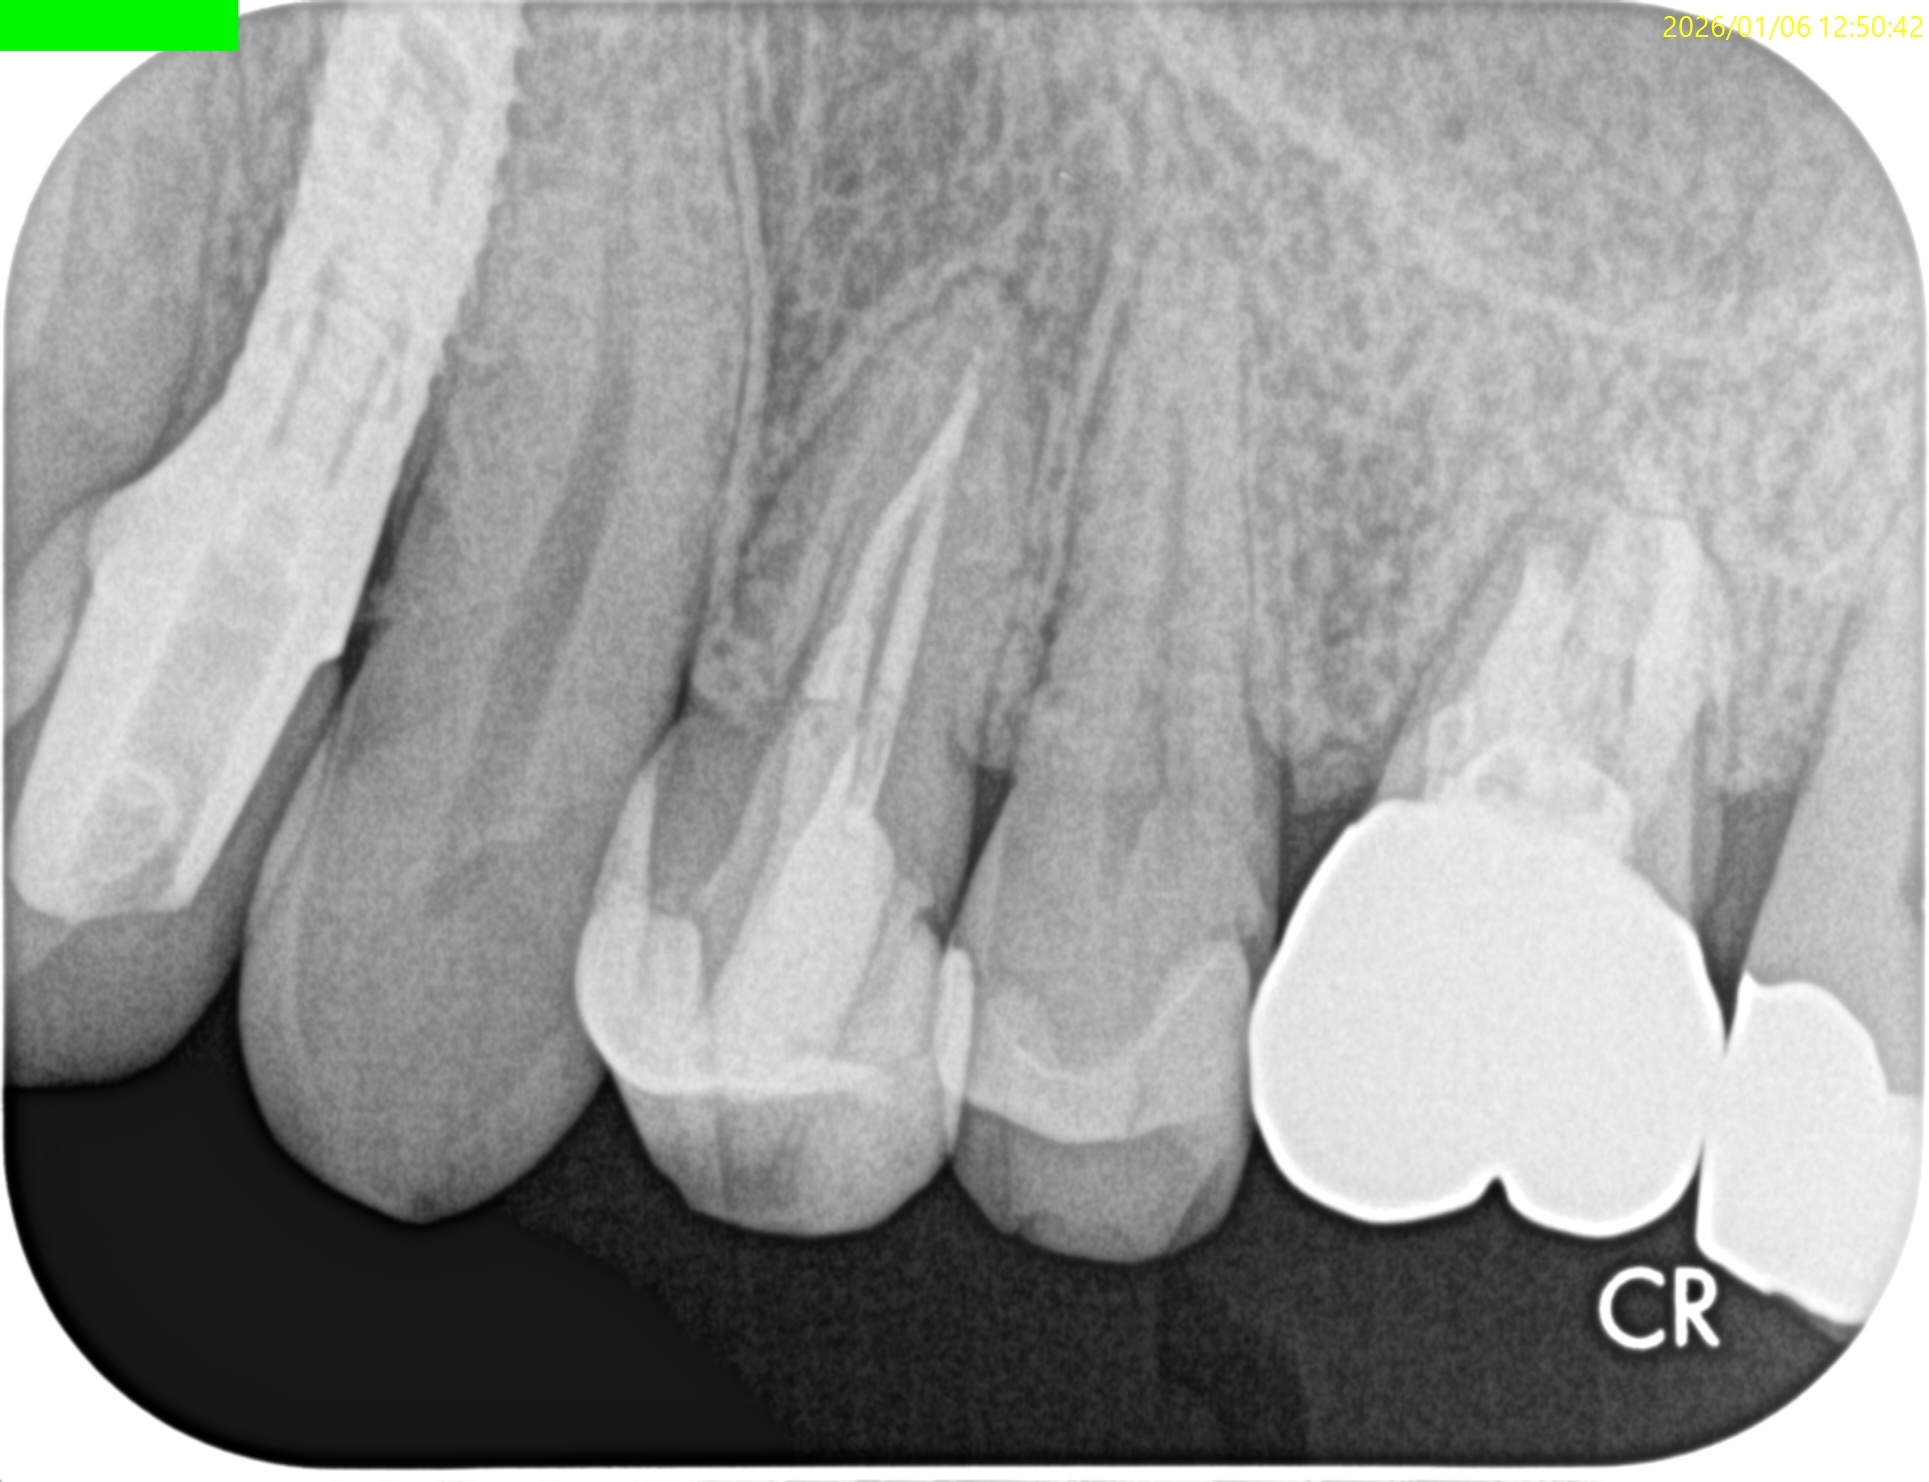

PA(2026.1.6)

Inlay除去後のCR修復は適合がいいとは決していえない感じだ。

2根管性で非機能咬頭のBが直線根管だ。

直覆のような処置がなされた形跡がある。

成人での直覆の成功率は低いことがすでにわかっていることから臨床症状と相まって#12 RCTが主訴の解決に寄与する可能性が高いだろう。